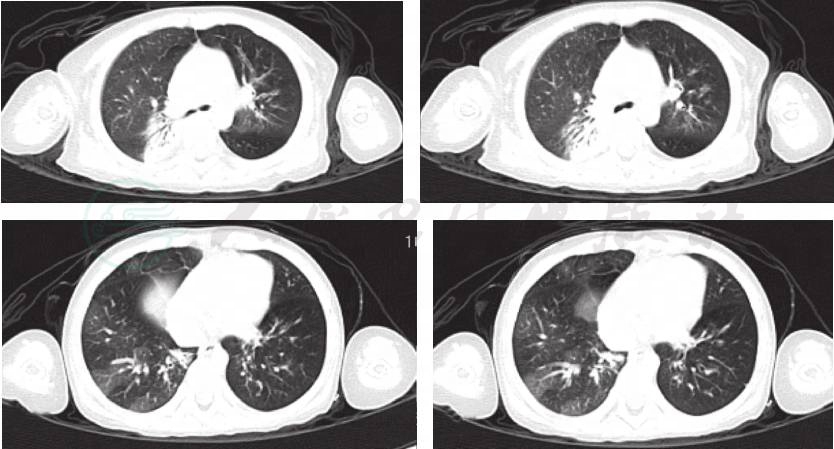

辅助检查:肺CT(当地医院,入院前2周)(图1):双肺透过度不均匀,双肺炎症,右肺部分实变。肺CT(笔者医院门诊)(图2A,图2B):双肺透过度不均匀,呈马赛克征改变,多叶段炎症,右肺部分实变,双肺散在肺气囊形成。

图1 入院前2周,当地医院肺CT

图2A 入院前笔者医院门诊肺CT

图2B 入院前笔者医院门诊肺CT

入院后完善各项检查:血常规、CRP等感染指标均正常;肺炎支原体抗体-IgM、IgG抗体均阴性;肺炎衣原体抗体阴性;结核抗体(TBAb)、常见呼吸道、肠道病毒及肝炎病毒检测均阴性,血细菌培养未见细菌生长,结核菌素试验阴性,G试验、GM试验阴性;免疫球蛋白及T淋巴细胞亚群无特殊异常。入院后予抗感染、布地奈德联合复方异丙托溴铵泵吸平喘治疗,但患儿喘息缓解不明显,结合病例特点及肺CT呈马赛克征改变,考虑为闭塞性细支气管炎,加用甲泼尼龙片[2mg/(kg·d),间隔 12 小时 1 次]、小剂量红霉素[5mg/(kg·d),每天2次]、乙酰半胱氨酸(600mg/次,每天1次)口服。期间患儿仍出现2次喘息加重及呼吸困难,均将口服甲泼尼龙片更换为静脉滴注甲泼尼龙琥珀酸钠[2mg/(kg·d)]、氨茶碱,患儿喘息略缓解。再次复查肺 CT(图3)示双肺多叶、段炎症部分吸收,右肺仍见部分实变改变较前未见明显变化,建议家属进一步完善支气管镜,行支气管肺泡灌洗术,以帮助明确病原,指导治疗,但家属拒绝。因患儿体温逐渐平稳,咳喘缓解,住院26天出院。出院医嘱:①口服甲泼尼龙片12mg,每天2次;②小剂量红霉素30mg/次,每天2次[5mg/(kg·d)];③乙酰半胱氨酸600mg/次,每天1次;④钙尔奇D 300mg/次,每天2次口服;⑤泵吸布地奈德0.25mg+生理盐水1ml/次,每天2次;⑥2周后门诊复查。

图3 入院后复查肺CT